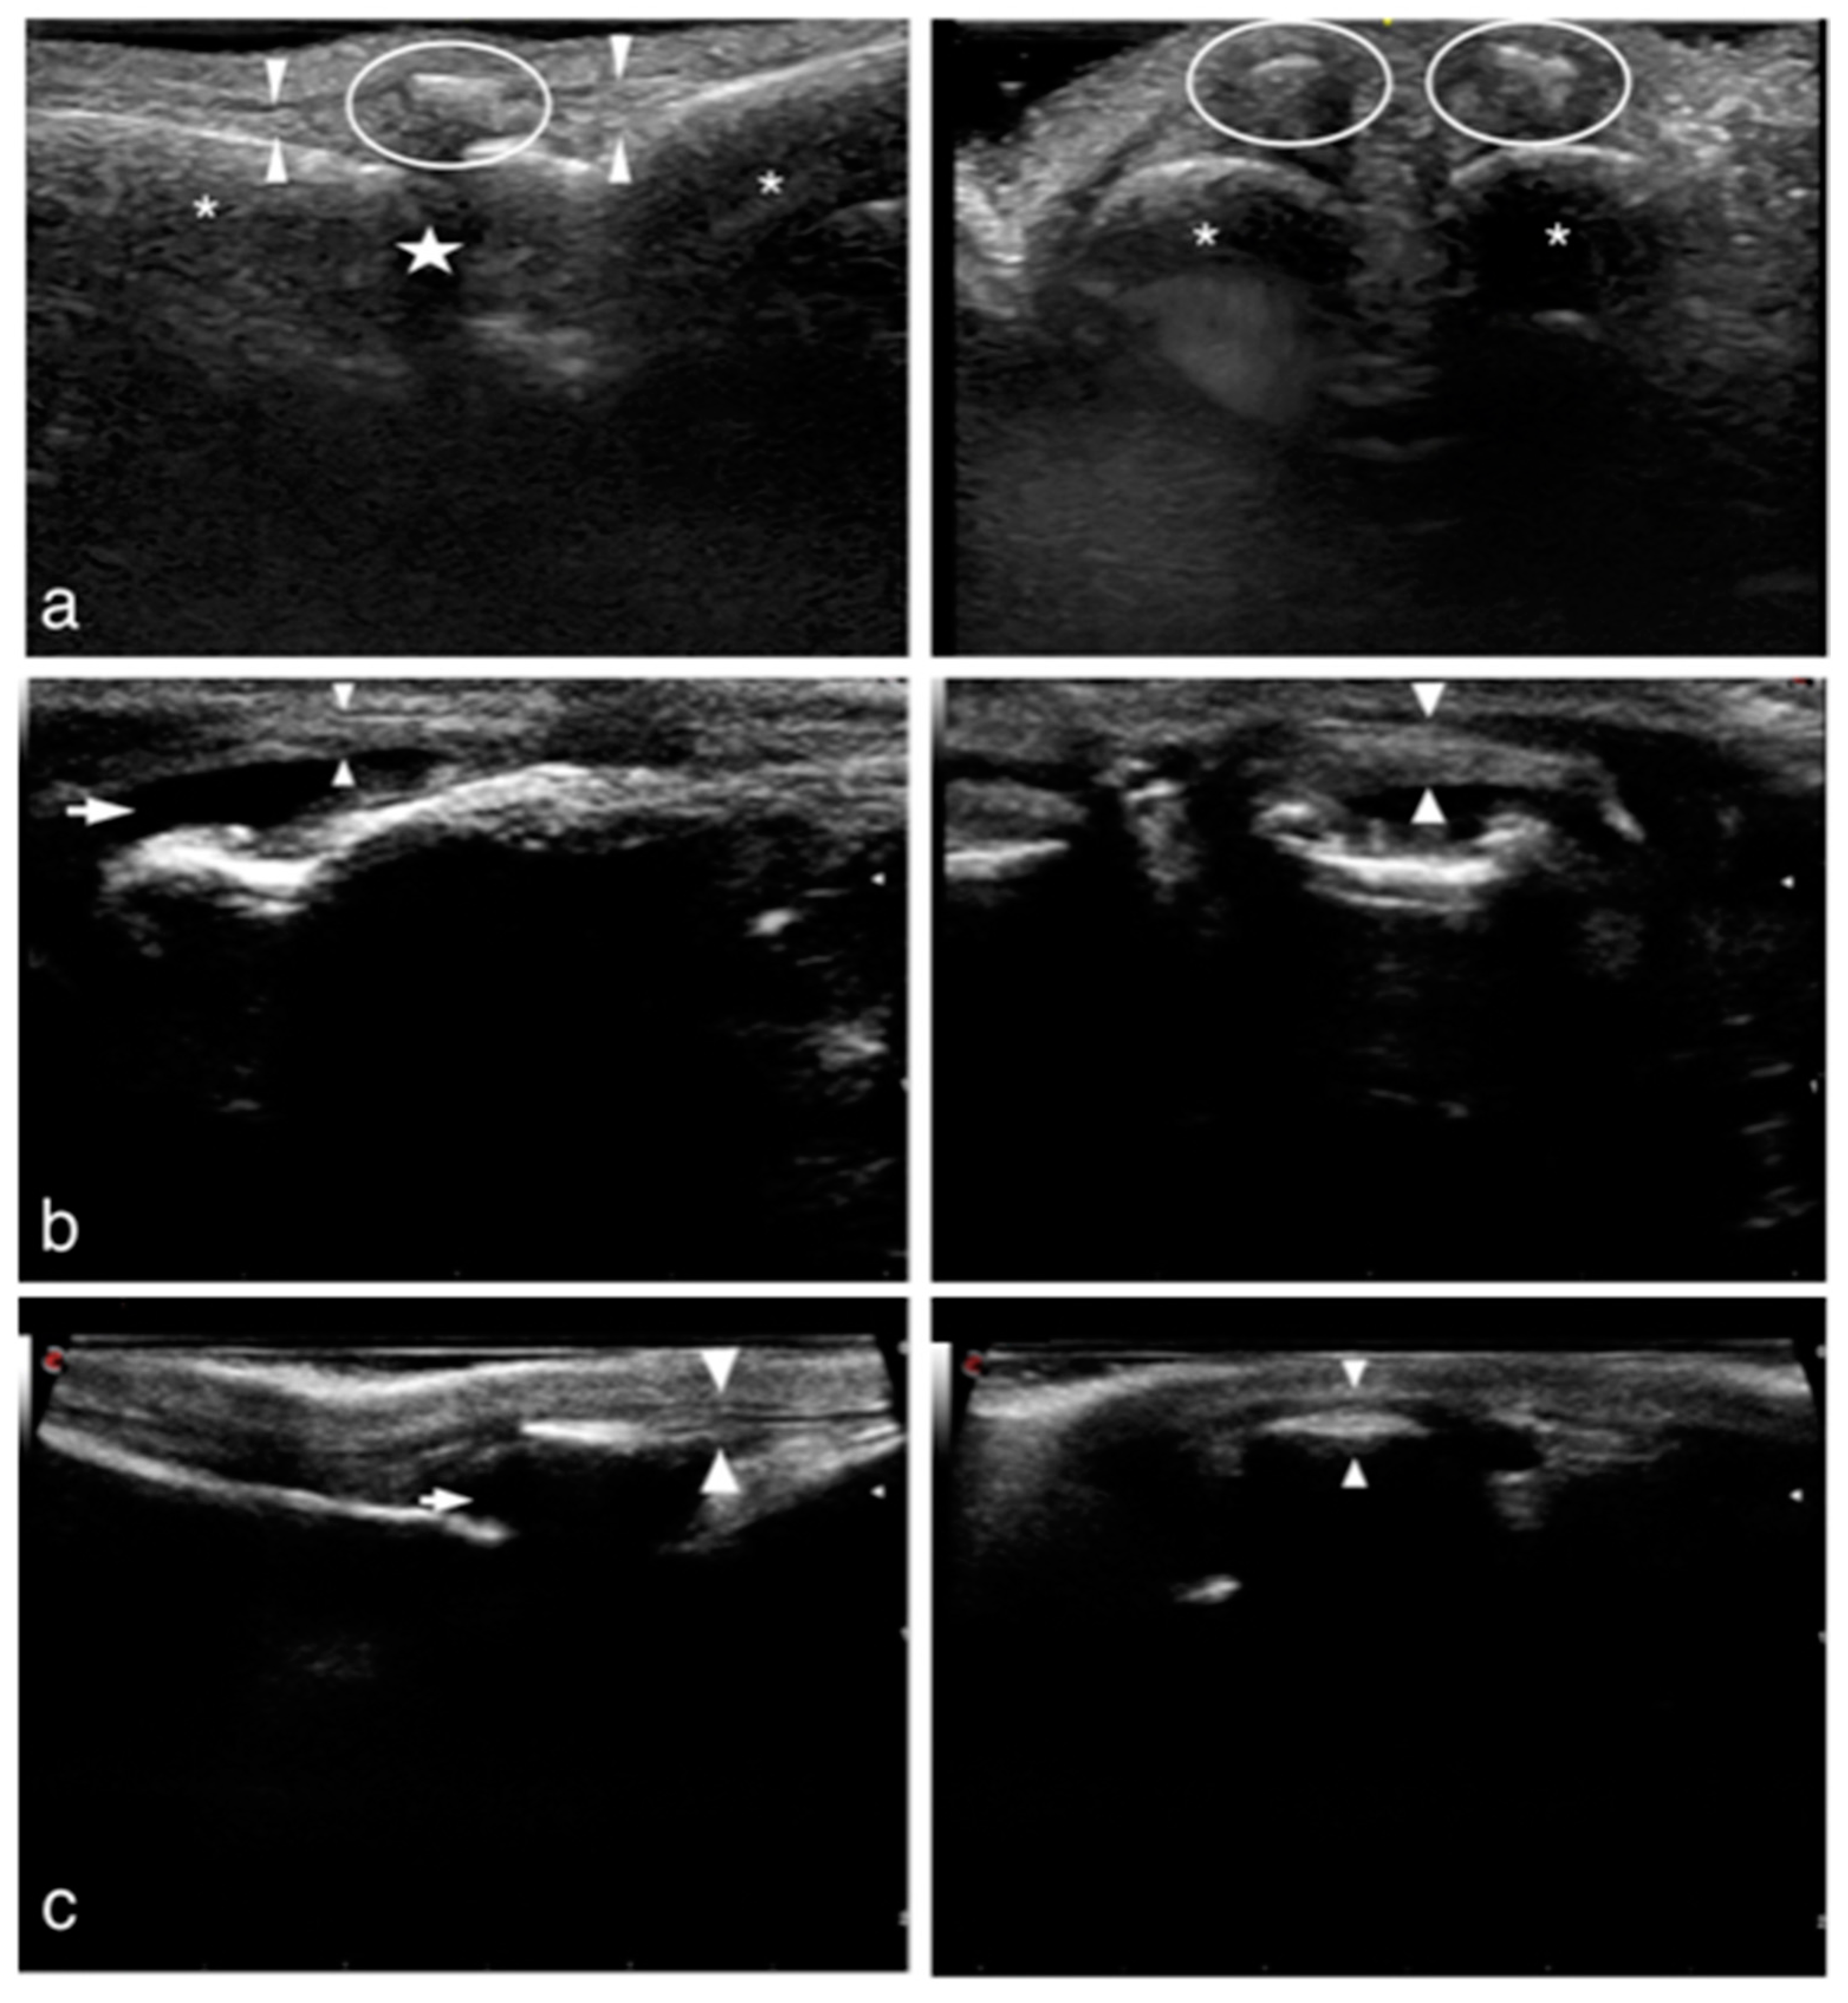

2.1.3. Ultrasonographic Examination (US)

2.2.3. Ultrasonographic Examination

2.3.3. Ultrasonographic Examination